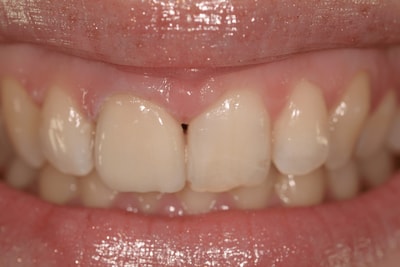

Situation Initiale